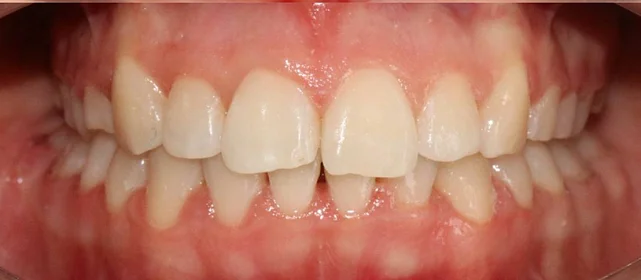

Зубы выровнены, смыкание нормализовано. Установлены несъёмные ретейнеры на обе челюсти, сняты сканы для ретенционных кап.

Решение: Поставили прозрачные элайнеры Click — начали с компактного набора из 20 кап. Основной комплект сделал основной объем работы, но для финальной доводки понадобился дополнительный набор из 10 кап. Итого 30 кап за 23 месяца. Результат — зубы на месте, смыкание в норме. Зафиксировали ретейнеры на обе челюсти, сняли сканы для ретенционных кап.

Небольшой по объёму случай — 20 кап в основном наборе. Этого хватило для основного выравнивания, но финальная коррекция смыкания потребовала ещё 10 кап. Предпочитаю доработать, чем оставить компромиссный результат. 30 кап за 23 месяца — спокойный темп, без спешки.